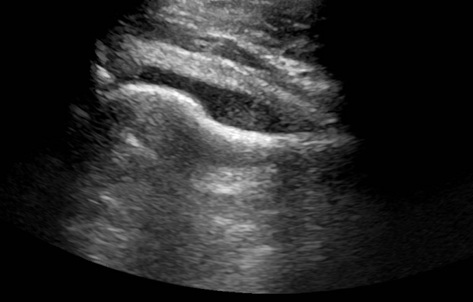

Image 1. US of the right hip joint showing moderate effusion.

A young man presented to the emergency department with the primary complaint of severe right hip pain persisting for 2 days. This pain began after standing uncomfortably for hours at an event. His right hip was tender to palpation with some erythema and swelling. He had no recent fall or known injury. He denied recent fever, chills, aches, constipation, diarrhea, changes in urinary habits, chest pain, and shortness of breath. An ultrasound (US) of the right hip joint showed moderate amount of effusion (Image 1). Laboratory results also showed an elevated white blood cell count (WBC).